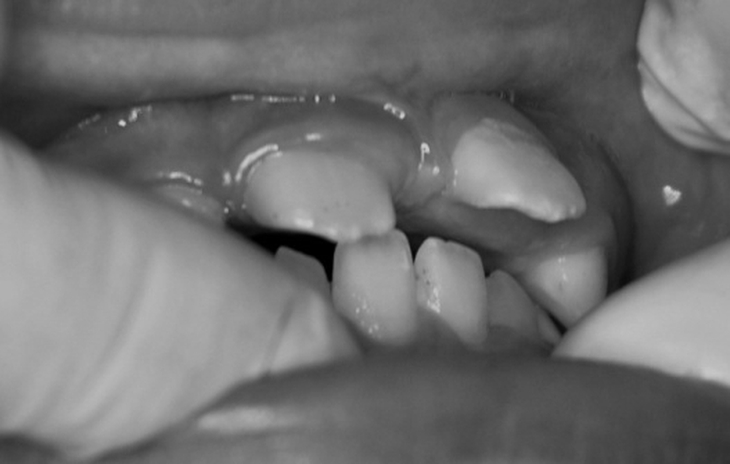

• Răng cửa trên vểnh ra ngoài, răng dưới cụp vào trong: Do lực tác động của ngón tay lên các răng cửa và xương hàm, khiến các răng mọc lệch hướng, tăng khoảng cách giữa răng trên và dưới.

• Khớp cắn hở: Khi trẻ mút ngón tay thường xuyên, các răng cửa trên và dưới không thể tiếp xúc khi cắn, dẫn đến cắn hở, gây khó khăn cho ăn nhai và phát âm. Khi khớp cắn hở, có thể dẫn đến hiện tượng đẩy lưỡi thứ phát.

• Hàm trên hẹp, biến dạng: Lực mút kéo dài làm cung hàm trên bị bóp lại, có thể gây cắn chéo hàm, ảnh hưởng thẩm mỹ khuôn mặt.

• Nhìn trong miệng thấy răng cửa trên vểnh ra, răng dưới cụp vào, có khe hở giữa hai hàm, răng mọc lệch, thậm chí trẻ nói ngọng.